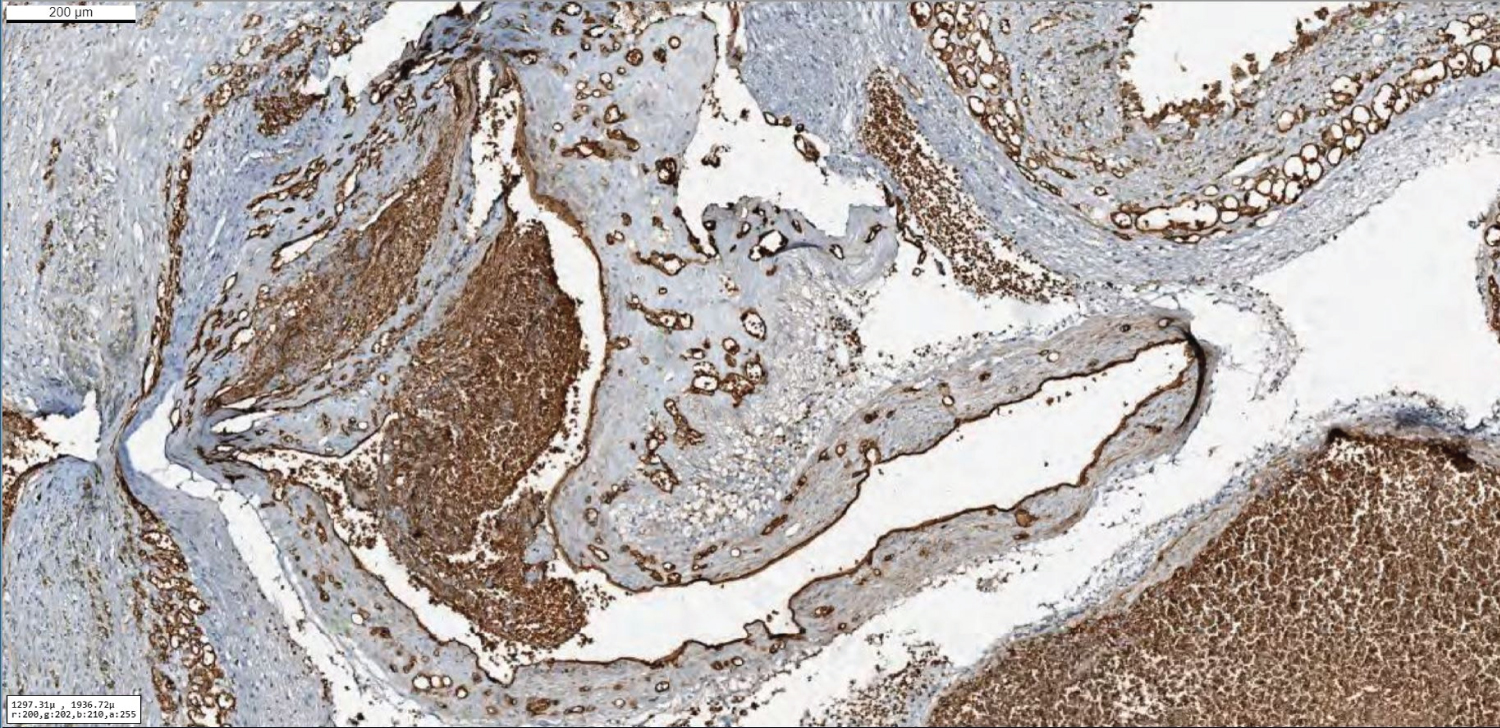

One percent of infantile hemangiomas involve the central nervous system, and approximately half of these are intracranial [8]. Most intracranial infantile hemangiomas classically involve the extra-axial basal cisterns, subarachnoid and ventricular spaces, and cavernous sinus [9]. Our case was demonstrating classically findings of infantile hemangiomas (Figure 5), but confirmation of hemangioma was made by immunohistochemical staining. Pathologic specimen was positive staining with GLUT1 and SMA which are reliable markers for infantile hemangioma. GLUT1 (Figure 6 and Figure 7), a glucose transporter present in normal capillary endothelial cells constituting the blood-brain barrier, is a particularly useful marker of infantile hemangiomas because it differentiates those from other vascular tumors and malformations that have been shown to lack GLUT1 [10]. Several other associated abnormalities have been observed in infants with infantile hemangioma, including arterial anomalies, ipsilateral cerebellar hypoplasia, Dandy-Walker malformation, Moya Moya-like proliferation of the internal carotid artery terminus [11] (Figure 6 and Figure 7).

Figure 6: Hematoxylin Eosin dying of the pontine mass. Specimen showed a vascular lesion within slight walls. View Figure 6

Figure 7: Immunohistochemically, Glut-1 dye showed expressions of the vascular wall and it's compatible with the infantile type hemangioma. View Figure 7